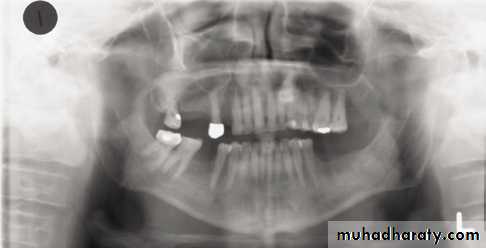

Patient too far forward; note spine superimposed over rami, blurring, and narrowing of anterior teeth